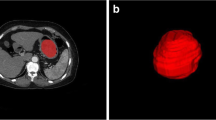

CT texture analysis

The three-phase enhanced CT images were uploaded into in-house software (Image Analyzer 2.0). All the images were reviewed by reader one. Polygonal ROIs in the arterial phase (mean size 401.63 mm2; range 34.80–2442.87 mm2), portal phase (mean size 363.47 mm2; range 41.12–2129.96 mm2), and delayed phase (mean size, 406.32 mm2; range 67.29–1891.79 mm2) CT images were manually segmented along the tumor contour on the largest cross-section (Supplementary Fig. S1). The normal gastric wall tissue and the gastric cavity contents were avoided. The details and definitions of generated CT texture parameters were listed in Supplementary Table S2. Texture parameters derived from ROIs delineated by reader one were used to predict HER2 status. Reader two repeated the above procedure to determine interobserver reproducibility.